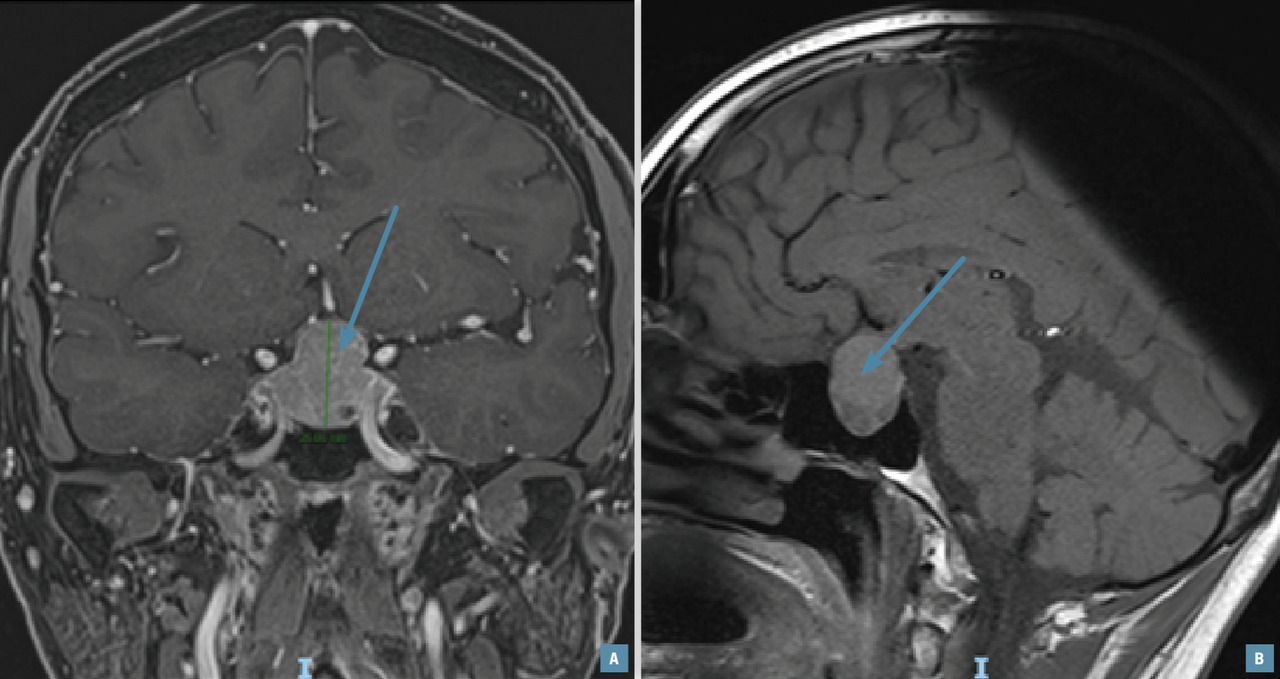

Lors de l’exploration d’une aménorrhée secondaire, une IRM hypophysaire (fig. 1) doit être réalisée en cas d’hypogonadisme hypogonadotrope, avec ou sans hyperprolactinémie.

Cet examen peut mettre en évidence des tumeurs de la région hypothalamo-hypophysaire, en particulier un adénome à prolactine, un méningiome ou un craniopharyngiome. En cas d’aménorrhée dite fonctionnelle ou nutritionnelle, l’IRM est normale ; ce diagnostic est retenu après avoir éliminé les causes organiques.